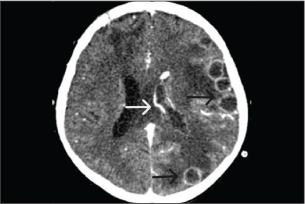

One week after surgery, follow-up brain CT showed enlargement of multiple ring-enhancing lesions in the left frontal, parietal, and occipital lobes, left lateral ventriculitis (Fig. 3). Intraventricular amphotericin B deoxycholate 0.5 mg once daily was added to his antifungal regimen for 14 days due to a lack of radiologic response to ongoing therapy. The fungal isolate was identified as Aspergillus fumigatus on Sabouraud dextrose agar media of abscess and CSF; greenish, powdery, non-velvety colonies and lactophenol cotton blue staining showed septate hyphae, dichotomous branching, columnar conidial head, flask-shaped vesicle, limited phialide upper half of two-thirds of the vesicle, and uniseriate conidia head. Polymerase chain reaction (PCR) analysis of the brain abscess confirmed Aspergillus fumigatus, while bacterial cultures and PCR were negative (Table 2). HIV testing was negative, and lymphocyte subset analysis (CD3, CD4, and CD8) and serum immunoglobulin levels (IgA, IgE, IgG, and IgM) were within normal ranges. Neutrophil oxidative burst testing (NBT) or Dihydrorhodamine test (DHR) and lymphocyte proliferation assays were deferred, as these tests should be performed at least 1 month after blood transfusion to ensure accurate results.

Fig. 3. A computed tomography scan of the brain with contrast on day 23 of admission showed two ring-enhancing lesions located in the left occipital lobe (black arrow) and left periventricular region, adjacent to the lateral ventricle (white arrow).